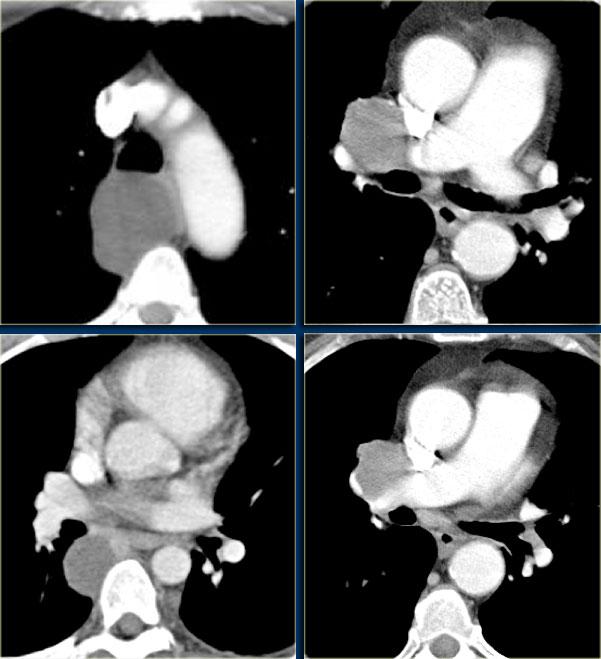

Tuyến ức phì đại có hình tứ giác với bờ bên lồi, thùy múi.

Phim ngực cho thấy các đặc điểm điển hình của u lympho Hodgkin, ví dụ: một khối trung thất trước.

Các hình ảnh CT của cùng bệnh nhân cho thấy một khối mô mềm lớn ở trung thất trước, xuất phát từ tuyến ức.

Có hạch cạnh khí quản kèm theo (mũi tên).

Hai trường hợp u lympho Hodgkin khác.

Các trường hợp này cũng cho thấy khối trung thất trước và hạch cạnh khí quản to.